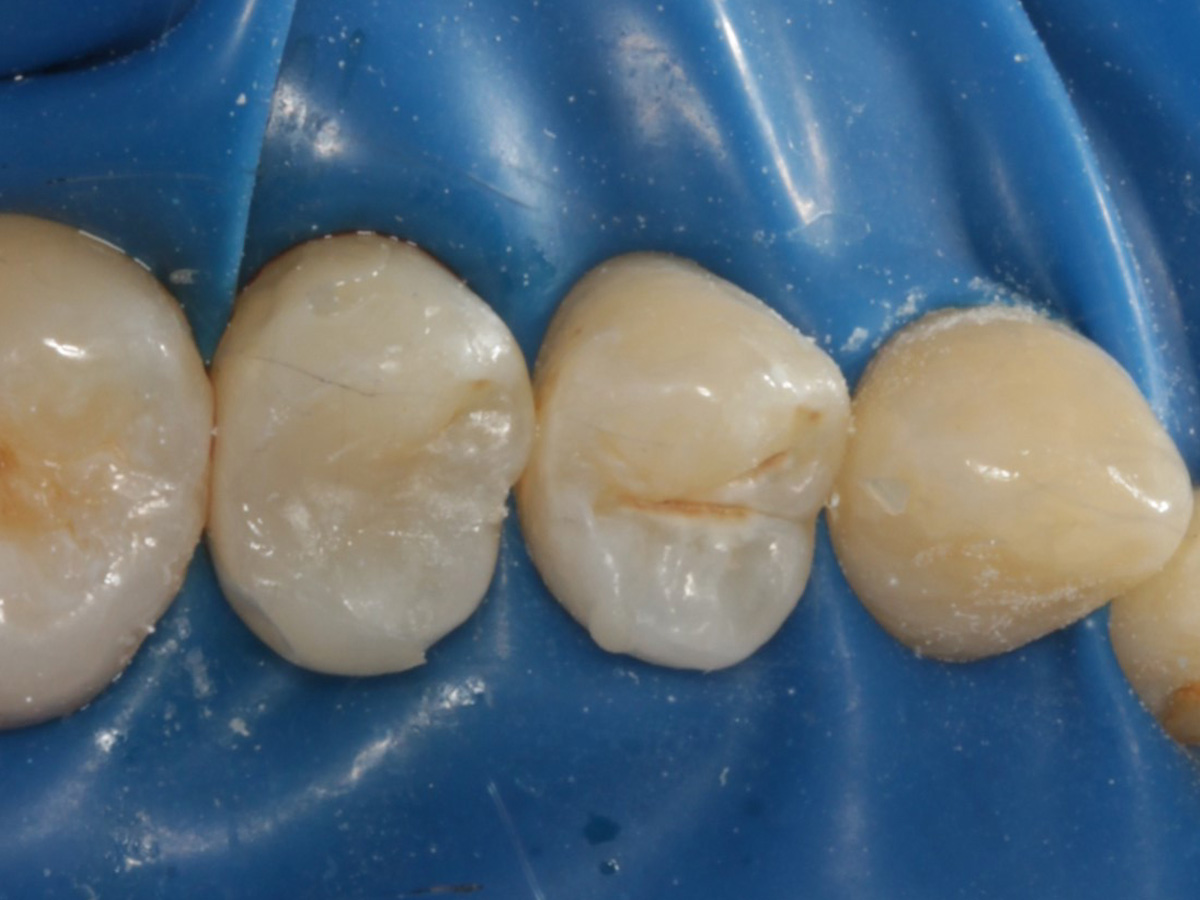

Abbildung 8

Nach Anschrägung der Schmelzränder und Reinigung der Kavitätenränder mit diamantierter Hubfeile

Abbildung 9

Height Indicator vor Auswahl der passenden Evolve Matrize